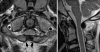

Background: The embryology of the bony craniovertebral junction (CVJ) is reviewed with the purpose of explaining the genesis and unusual configurations of the numerous congenital malformations in this region. Functionally, the bony CVJ can be divided into a central pillar consisting of the basiocciput and dental pivot and a two-tiered ring revolving round the central pivot, comprising the foramen magnum rim and occipital condyles above and the atlantal ring below. Embryologically, the central pillar and the surrounding rings descend from different primordia, and accordingly, developmental anomalies at the CVJ can also be segregated into those affecting the central pillar and those affecting the surrounding rings, respectively.

Discussion: A logical classification of this seemingly unwieldy group of malformations is thus possible based on their ontogenetic lineage, morbid anatomy, and clinical relevance. Representative examples of the main constituents of this classification scheme are given, and their surgical treatments are selectively discussed.